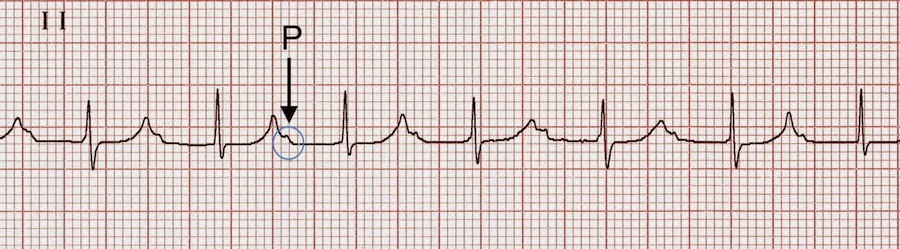

Mat with av block ecg.

The rhythm is atrial tachycardia with complete av block. It is typically a transitional rhythm between frequent premature atrial complexes pacs and atrial flutter fibrillation. Multifocal atrial tachycardia mat overview a rapid irregular atrial rhythm arising from multiple ectopic foci within the atria. This interruption of impulse transmission results in characteristic ecg findings that different depending on the sub type of av block.

Multifocal or multiform atrial tachycardia mat is an abnormal heart rhythm specifically a type of supraventricular tachycardia that is particularly common in older people and is associated with exacerbations of chronic obstructive pulmonary disease copd. Atrioventricular av block often referred to as heart block involves the partial or complete interruption of impulse transmission from the atria to the ventricles. The ecg above is from a 83 years old woman who had applied to the hospital 2 days after acute anterior wall myocardial infarction. First degree av block with normal qrs complex qrs duration 0 12 s is localized in the av node in 90 of the cases and the bundle of his in 10 of cases.